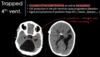

4TH VENT OBSTRUCTION:

-causes?